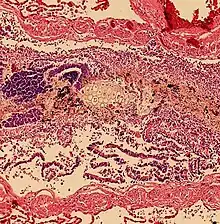

Aspiration Pneumonitis

Aspiration pneumonitis (Mendelson's syndrome) is chemical injury of lung tissue secondary to aspiration of regurtitated gastric acid.[15] The syndrome was first described among pregnant patients[16] after the administration of anesthesia, though it can occur in any scenario where gastric contents are aspirated.[17]